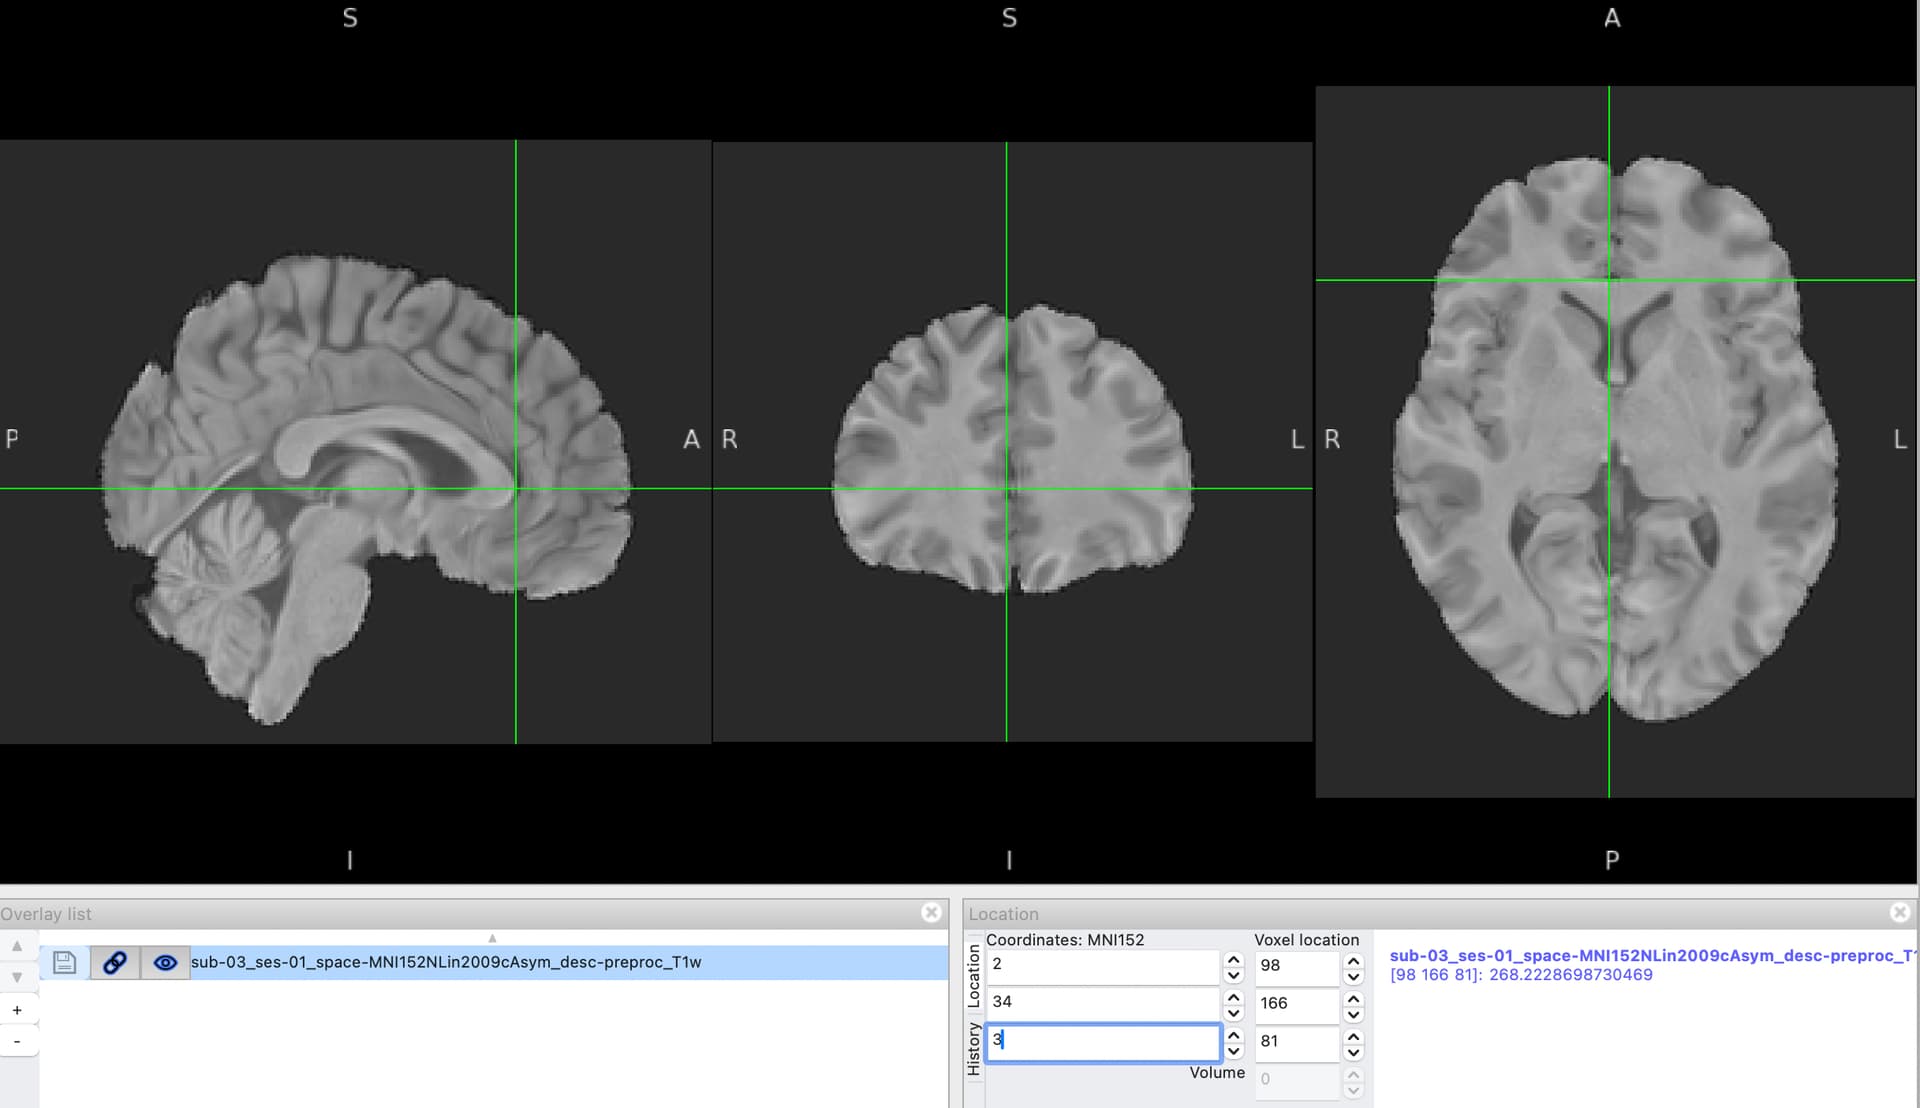

but after transformation, some cords were out of the brain region of the sub-1_ses-1_desc-preproc_T1w.nii.gz. What’s the problem, am I missing something? and if so, what’s the best solution for converting the cords from MNI to unprocessed subject space?